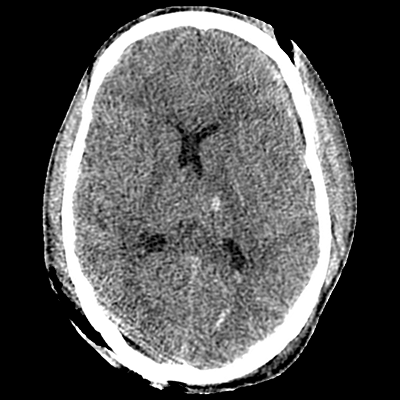

A 35 year-old man with no medical history was originally brought to the ED this morning after being a restrained driver in a motor vehicular collision. Initial GCS was 3, and he was intubated in the field by EMS. He underwent whole-body cross-sectional imaging. His head imaging is shown below. Neurosurgery was consulted and placed a right frontal intraparenchymal monitor. He was admitted to the NCCU.

Non-contrast head CT demonstrating IVH, DAI, scalp hematoma